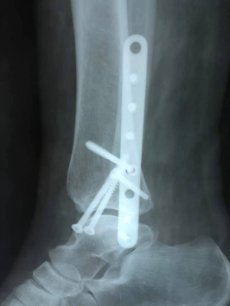

Завдяки вчасному зверненні та професіоналізму лікаря-ортопеда-травматолога, жінку вдалося врятувати. Волинянка з необережності впала на власному городі. В ургентному порядку жінку доставили в КНП «НЦМЛ». Після огляду лікар встановив діагноз: відламковий перелом кісточок гомілки з вивихом стопи.

Пацієнтці виконали відкриту репозицію уламків з внутрішньою фіксацією. Операція пройшла успішно.

"В операційній працювали: лікар-ортопед-травматолог Родзь Тарас Яремович, анестезіолог Міщук Оксана Миколаївна, сестра медична операційна Магдюк Людмила Анатоліївна. Дякуємо нашим медикам за врятоване життя", - йдеться в дописі.